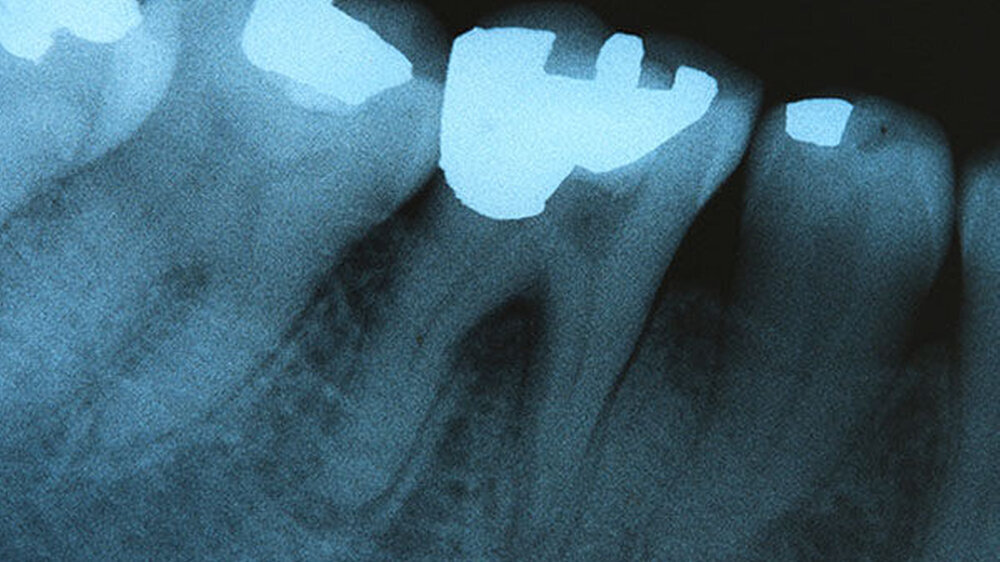

Darüber hinaus schreibt das BMG: „Grundsätzlich spricht für eine Verwendung von Amalgam, dass es sich um ein anerkanntes und wissenschaftlich gut untersuchtes Füllungsmaterial handelt. Seine Verarbeitung ist im Vergleich zu Kompomeren und Kompositen weniger technikintensiv und aufwändig. In Longitudinalstudien weist es eine hohe Lebensdauer auf.“

Der Anteil der Füllungen mit Amalgam lag dem BMG zufolge 1997 bei rund 58 Prozent und im Jahr 2005 bei 43 Prozent aller Bestandsfüllungen. Schreibe man diesen Trend weiter fort, könne man davon ausgehen, dass der Anteil der bereits ausgeführten Füllungen mit Amalgam derzeit weniger als 30 Prozent aller Bestandfüllungen beträgt und sich aufgrund des geringen Anteils der neu gelegten Amalgamfüllungen und des Erfolgs der Prävention sukzessive weiter verringern dürfte.